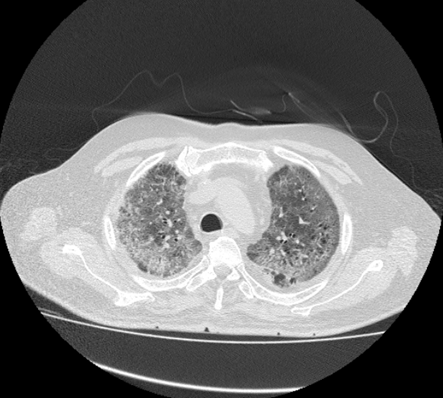

In most of the patients with COVID pneumonia, the tomographic findings show ground-glass opacity (GGO). In almost all the CT images of COVID patients, the GGO is prominent, which reflects that it is almost present in all samples and thus reflects the presence of COVID, and probability reflects the early stage. (Figure 2)

Figure 2 Spatial Thickness found in CT Image 2.